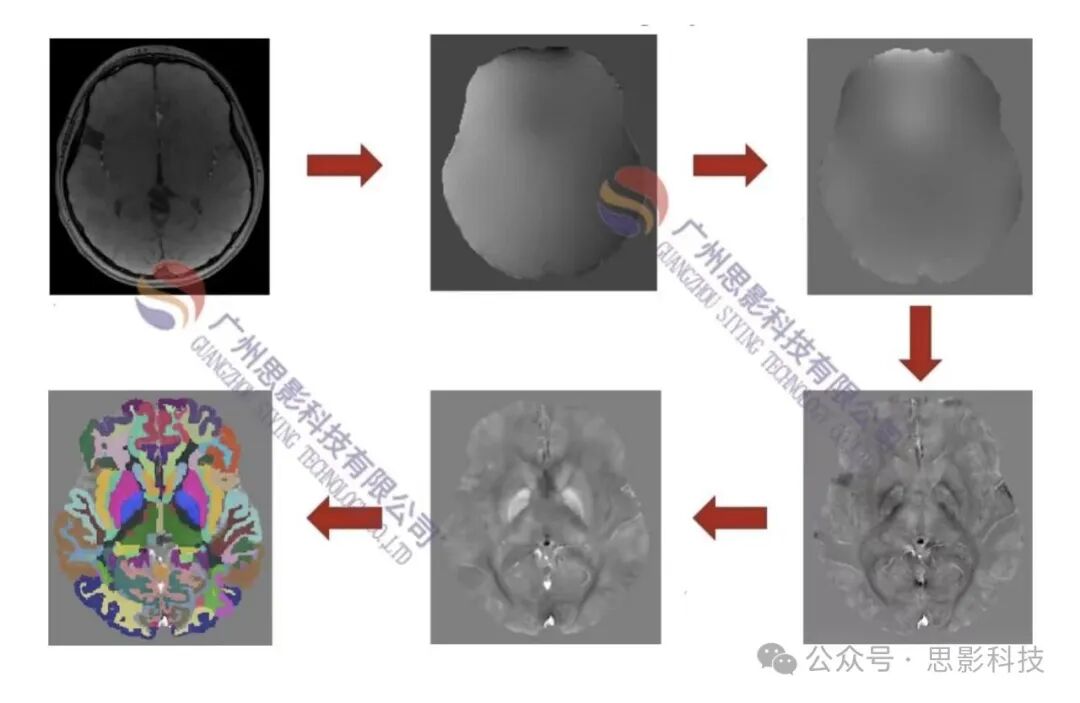

随着算法和计算能力的提升,新型的QSM重建算法能够有效地提高图像质量和重建精度,从而进一步提升临床和科研应用的可靠性和准确性。为此,我们推出了定量磁敏感成像(QSM)数据分析班,系统讲解QSM的原理与应用,涵盖最新的QSM数据处理方法,包括基于软件界面的QSM图像重建、基于代码的QSM图像重建,以及QSM图像的后处理(配准+平滑)、统计分析与可视化技术。培训班还将介绍如何在 QSM 数据中应用组间比较、回归分析等统计方法。

内容主要包括:QSM方法介绍、QSM分析流程、基于软件界面和代码的QSM数据处理实操、QSM图像后处理(配准+平滑)、组水平统计分析、绘图等。

l 基于软件界面的QSM数据处理 l QSM图像重建 |

l 基于代码的QSM数据处理 l QSM图像重建的批处理 |